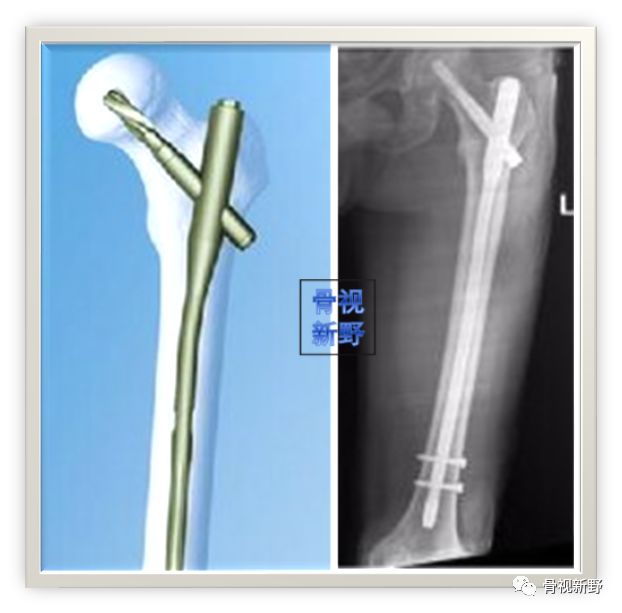

尖-顶距(Tip-Apex Distance ,TAD)<25mm

无论用髓内钉或钉板系统,TAD是评估头钉深度和居中程度的重要指标;也是预测反转子骨折固定成功最重要的指标。过去,旧的理论主张偏下、偏后置钉,这样会使前、上股骨头内保留较多骨量,但会增加TAD,现代理论建议避免。